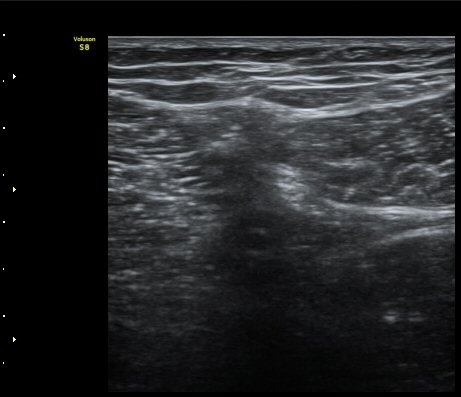

ŽÃËÀÚ¸¦ ¸»´ÜÀ¸·Î À̵¿ÇÏ´Ï º¹Àç½Å°æÀÌ ½½°³°ñÇϰ¡Áö¿Í  ºÀ°ø°¡Áö(sartorial branch)·Î

°¥¶óÁö´Â °ÍÀÌ °üÂûµÇ°í(»çÁø 3, 4, 5) µ¿¿µ»ó È­¸éÀ¸·Î º¸¸é ´õ¿í ¶Ñ·ÈÇÏ´Ù(÷ºÎ ÆÄÀÏ 1)

º¹Àç½Å°æ ½½°³°ñÇϰ¡Áö°¡ È®ÀÎµÈ »óÅ¿¡¼­ ´ëÅð ¾Õ¿¡¼­ ÃÊÀ½ÆÄÀ¯µµÇÏ ½½°³°ñÇϰ¡Áö

Â÷´ÜÀ» ½ÃÇàÇÏ¿´´Ù(÷ºÎ ÆÄÀÏ 2).